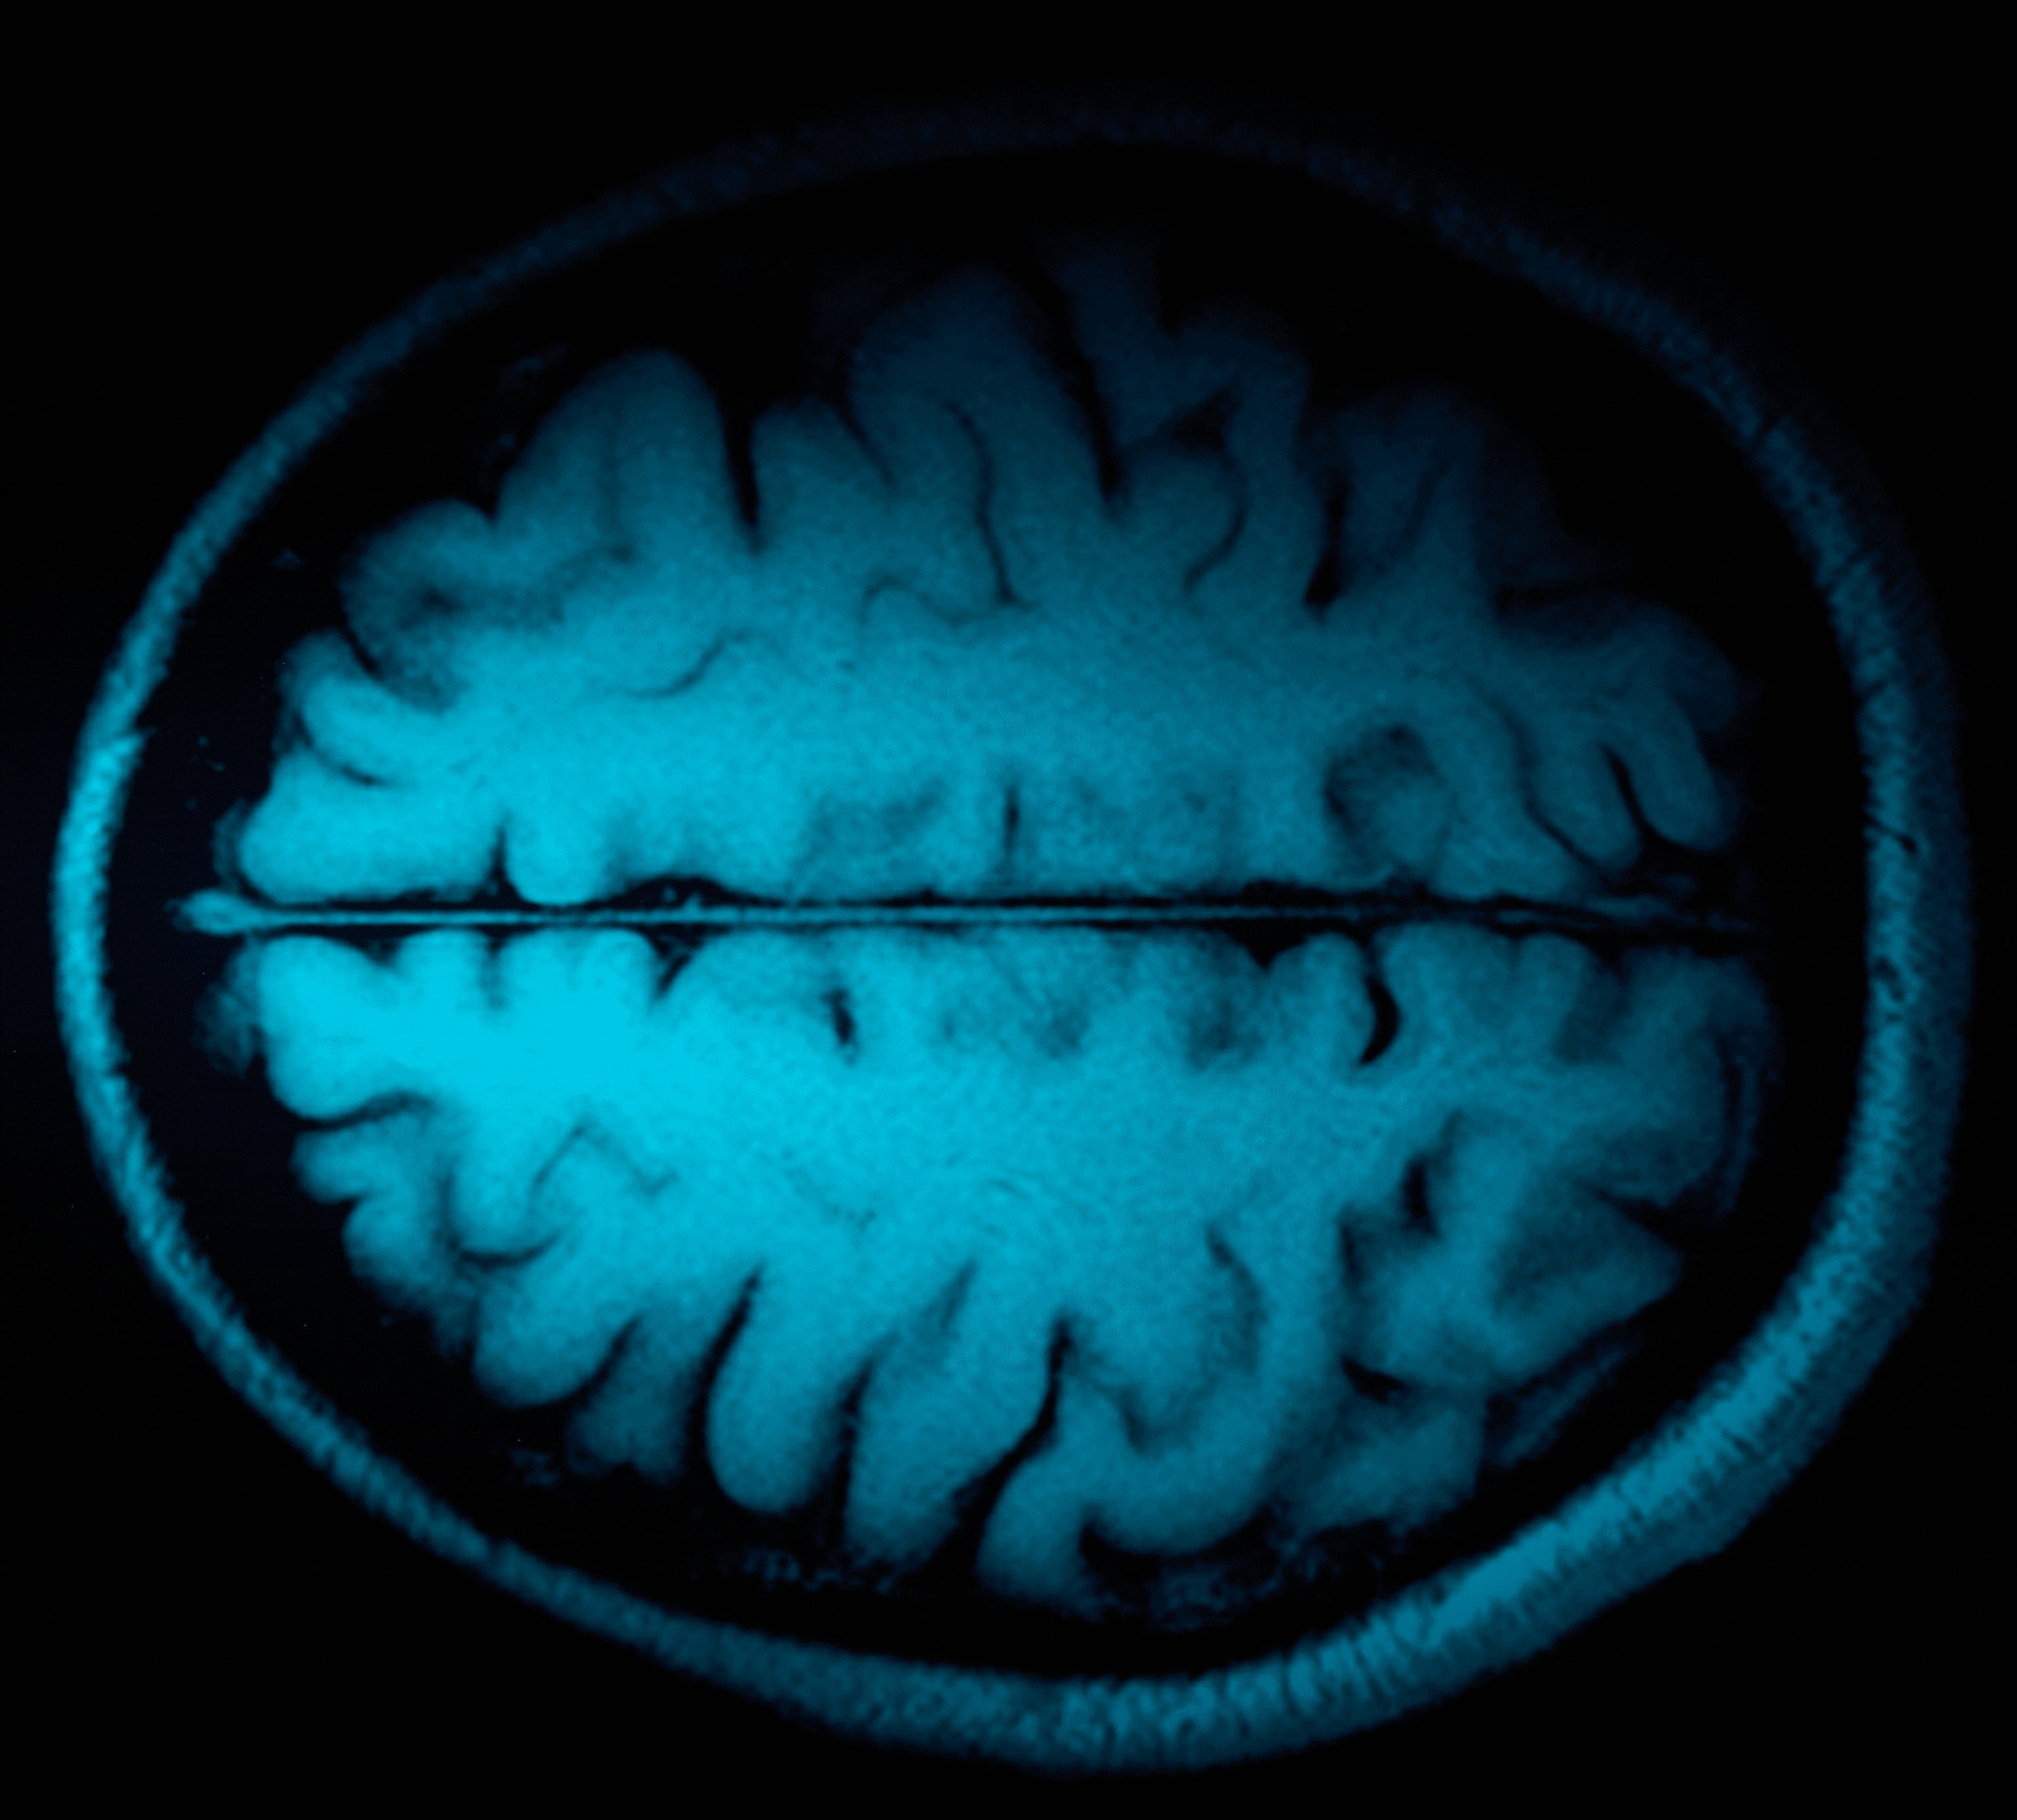

Their findings, recently published in a Nature Medicine study, show the results of machine learning and brain imaging in hundreds of patients while doing specific tasks and at rest—helping the team identify six distinct subtypes of depression.

To help, the Stanford researchers used functional magnetic resonance imaging (fMRI) technology to study the regions of the brain most commonly associated with depression such as the amygdala, hypothalamus, hippocampus, and prefrontal cortex, and, more importantly, the connections—called circuits—between those brain structures.

The researchers measured these disrupted functions as they relate to depression by scanning the brains of 801 study participants who had already been diagnosed with depression or anxiety, then studying their brain activity while at rest and while they engaged in different tasks designed to stimulate cognitive function or emotional responses to various situations—dual explorations that haven't been studied this way before.

"By quantifying brain function at rest and during specific tasks, we have shown that depression consists of six specific patterns of dysfunctions in six major brain circuits," says Williams.